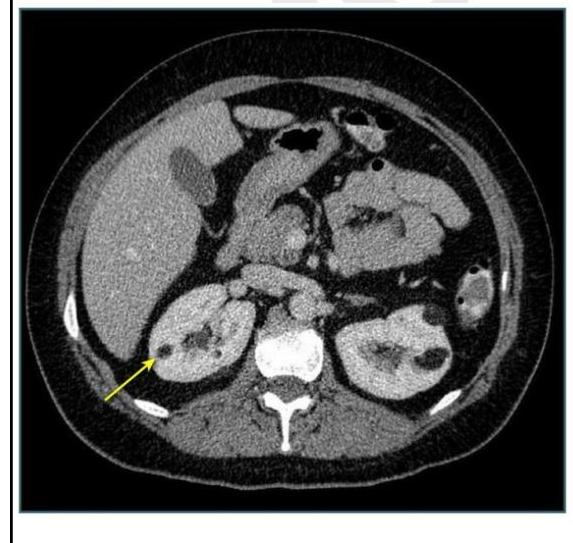

A 45-year-old patient presented with vague abdominal pain. On USG, he was found to have a renal cyst of Bosniak class III. CECT was done, as shown below. What imaging modality is shown?

Explanation: ***CT scan*** - The image provided is an **axial view** showing internal organs with different densities, characteristic of a **Computed Tomography (CT) scan**. - A CT scan uses X-rays and computer processing to create detailed cross-sectional images of the body. *Contrast Dye study* - A contrast dye study typically refers to the **administration of a contrast agent** to enhance visibility of structures in imaging, it is not an imaging modality itself but an adjunct. - While a CECT (Contrast-Enhanced CT) was mentioned in the clinical scenario, "Contrast Dye study" alone doesn't describe the image type. *Angiography* - **Angiography** is a specialized imaging technique used to visualize blood vessels, typically involving the injection of contrast media. - The image provided shows **parenchymal structures** like the liver and kidneys, not just blood vessels, making angiography an unlikely description. *X-ray* - A general **X-ray** (radiograph) produces a 2D projection of internal structures and does not provide the detailed cross-sectional view seen in this image. - X-rays are typically less sensitive for soft tissue differentiation compared to a CT scan.